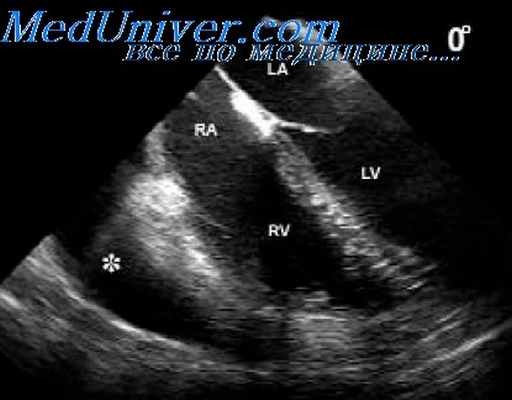

С помощью эхокардиографического исследования возможно визуализировать дефект межпредсердной перегородки, уточнить его характер (первичный или вторичный), оценить направление сброса через дефект (рис. 6, 7).

С помощью эхокардиографии возможно подтвердить наличие ДМПП, определить анатомическое расположение и размер дефекта, а также оценить степень перегрузки объемом правого предсердия и правого желудочка.

Возможность ультразвукового метода, в первую очередь, определяется непосредственной визуализацией дефекта при исследовании в реальном масштабе времени. Для оценки наличия, расположения и размеров дефекта необходимо проводить исследование из многих позиций. Исследование в четырехкамерной позиции не всегда позволяет увидеть вторичный дефект, т.к. межпредсердная перегородка в этом срезе расположена параллельно ультразвуковому лучу.

Акустические тени и выпадение эхо-сигналов создают основу для ложно-положительного заключения. (Feigenbaum H., 1999). При субкостальной четырехкамерной позиции диагностика вторичного дефекта более надежна, а также в этой позиции можно дифференцировать первичный, вторичный и дефект венозного синуса и визуализировать аневризму межпредсердной перегородки. Последнее очень важно, ибо аневризма представляет потенциальную возможность прикрепления тромба с вогнутой стороны (Wysham D.G.et al., 1984).

- Трансторакальная эхокардиография позволяет не только визуализировать дефект межпредсердной перегородки и уточнить его характер (первичный, вторичный, дефект венозного синуса), но также оценить направление сброса крови через дефект и его гемодинамическую значимость (Qp/Qs).

- Чреспищеводная эхокардиография у взрослых позволяет получить детальную информацию о краях дефекта, что важно для выбора метода оперативного лечения.